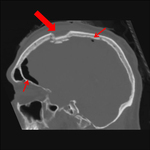

Sagittal CT images of an open, comminuted, depressed skull fracture. Note the associated pneumocephalus (small arrows). The level of depression is greater than the bony table and there are several bone fragments impacted below the inner cortex of the opposing bone (large arrow). Despite lack of underlying associated brain injury this fracture required operative debridement and elevation of the bone fragments. See also the corresponding coronal CT image

From the teaching collection of Demetrios Demetriades; used with permission